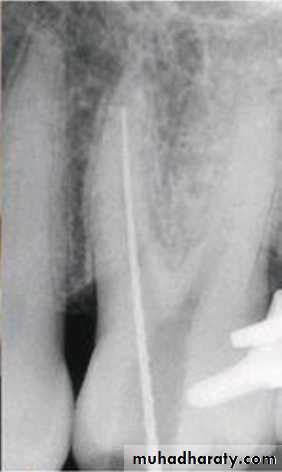

Hand instruments manipulation

• Filing:

Is the push and pull movement of a file within the canal. K-files and H-files can be used for this movement, the later has better cutting efficiency.

• Reaming:

Is the quarter turn and pull movement, it could be used by reamer or file, the quarter turn is rotated clockwise to engage the canal dentin and the pull movement is to cut this dentin off the wall. H-file is contra indicated for reaming due to possibility of fracture.

• Watchwinding

or a continuous back and forth rotation with slight apical pressure, with this movement a fine file rapidly advances down a root canal. Only fine files should be advanced to the apex in this way as there is a danger of compacting pulpal debris ahead of the file.• Circumfrential filing:

a push-pull filing movement circumferentially around the canal walls. K-files and H-files are used with an attempt to file on the outstroke only, to reduce the apical compaction of debris.Blanced force technique (Roane Tech):

Uses Flex-R (modification of K-files with non cutting tip) files in sequential order in a clockwise-counterclockwise-clockwise manner.• Step 1: After pressureless insertion of a Flex-R or NiTiFlex K-file, the instrument is rotated clockwise 90 degrees using only light apical pressure.

• Step 2: The instrument is rotated counterclockwise 180 to 270 degrees; sufficient apical pressure is used to keep the file at the same insertion depth during this step. Dentin shavings are removed with a characteristic clicking sound.

• Step 3: This step is similar to step 1 and advances the instrument more apically.

• Step 4: After two or three cycles, the file is loaded with dentin shavings and is removed from the canal with a prolonged clockwise rotation.